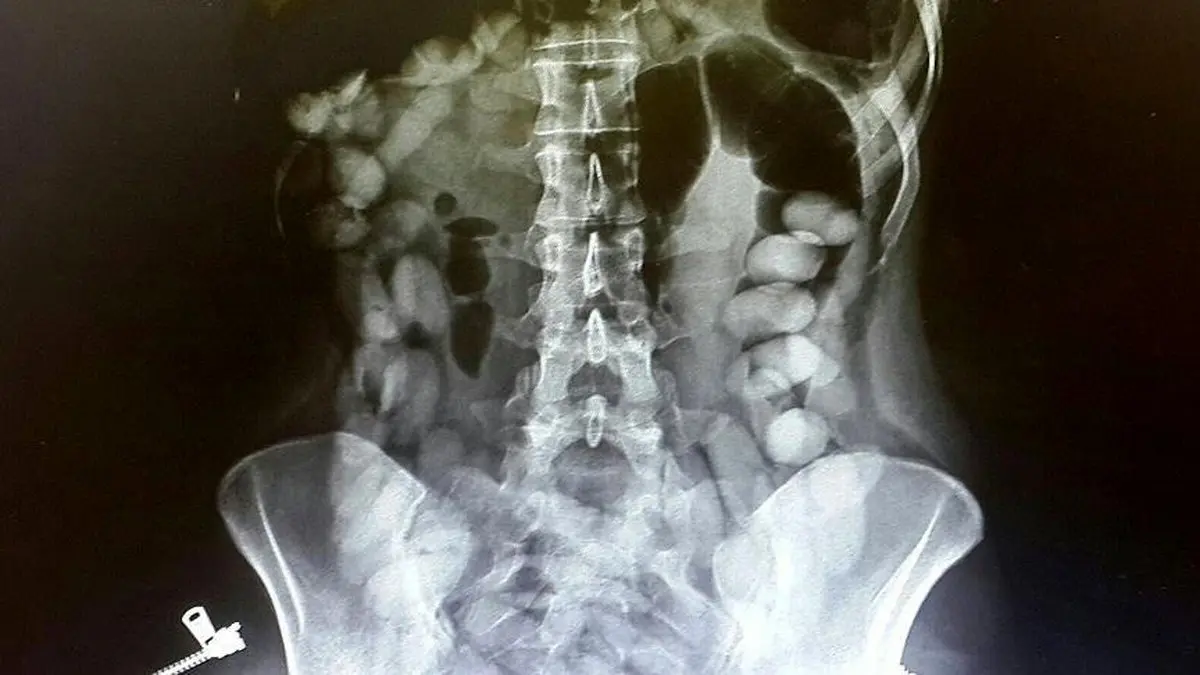

رئیس پلیس مبارزه با مواد مخدر فراجا ادامه داد: هم روش بلع مواد را داریم و هم سایر شیوههایی که مورد استفاده حاملان مواد مخدر است.

رئیس پلیس مبارزه با مواد مخدر فراجا با اشاره به روش شناسایی این نوع قاچاق مواد مخدر، تصریح کرد: تجهیزات پیشرفتهای در این رابطه وجود دارد که به راحتی میتواند تشخیص دهند.